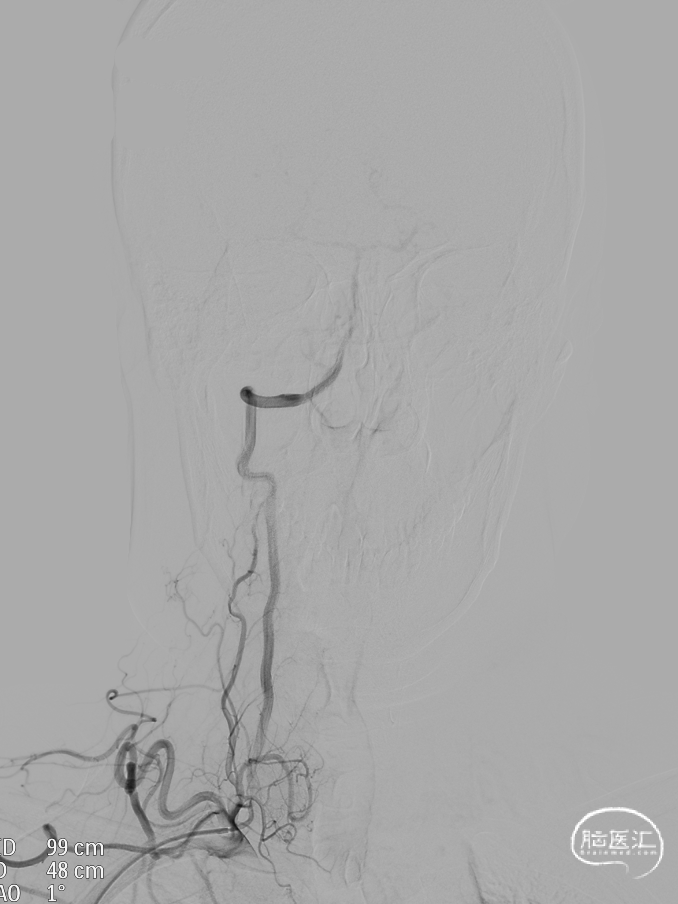

DSA:DSA提示右侧颈内动脉C6段可见多发动脉瘤。

其他血管造影未见明显异常。

术前诊断:右侧颈内动脉C6段多发动脉瘤。

治疗方案:血流导向装置植入术。

载瘤动脉远端血管直径:4.0mm

载瘤动脉近端血管直径:4.9mm、4.5mm(两个角度)